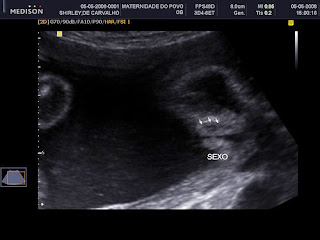

Esses anos para mim não foram fáceis. Em julho de 2006 fui estuprada grávida de dois meses por um maníaco que graças ao meu bom Deus está preso. Em agosto de 2007 minha filhinha de 7 meses de idade, faleceu. Estou grávida de outra menina que irá nascer em Agosto. Tudo isso eu estava com ele. Passamos por isso juntos, um apoiando o outro. Ou pelo menos eu achei...

Todo mundo sabe que sempre vai doer. Sempre vai ser ruim e que vai passar... Mas e aí? E até passar essa dor como eu fico sofrendo? E minha filhinha aqui na minha barriga que está também sofrendo por mais que eu tente e nao queria....